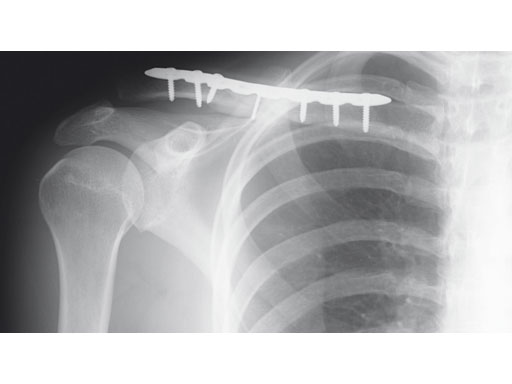

A 22-year-old man sustained an open clavicle fracture after a motorcycle injury.

Fig 1ab Preoperative x-rays.

Fig 2ab Postoperative images.